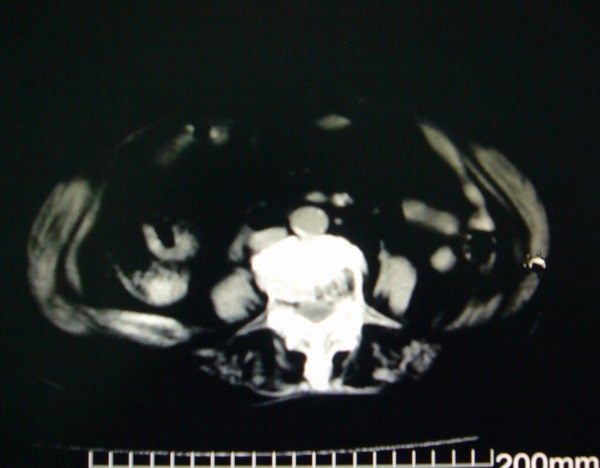

女:83y,转移性右下腹痛2小时,白细胞计数增高。

1.右侧肾盂扩大,肾盏无扩张,考虑:先天性肾盂变异可能性大。

2.胆囊扩张,考虑:胆囊炎。

3.阑尾区域可见以结节样高密度影,结合病史,考虑:阑尾结石,阑尾炎。

右下腹肠系膜增厚,结合病史支持阑尾炎.

右侧壶腹型肾盂可能,建议输路造影或增强

1.右侧肾盂扩大,考虑先天性肾盂变异或肾盂旁囊肿。

2.胆囊扩张,考虑胆囊炎。

3.阑尾区域可见结节样高密度影,结合病史考虑:阑尾结石、阑尾炎。